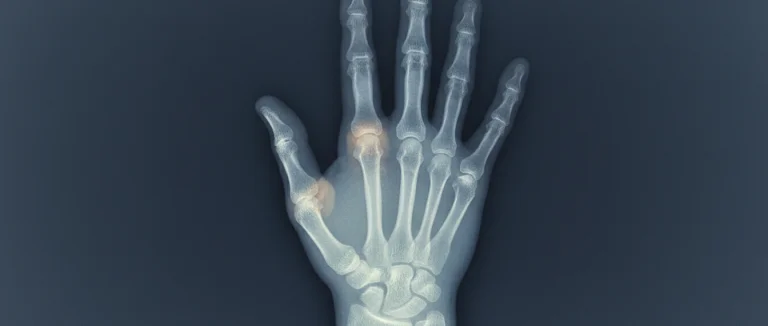

Точная диагностика – фундамент успешного лечения пальцев при ревматоидном артрите. На ранних стадиях заболевание может проявляться лишь небольшими изменениями, поэтому важно использовать комбинированный подход, включающий клиническое обследование и современные визуализирующие методы.

| Рентген (X‑ray) | Эрозии костей, узкие суставные пространства | Доступность, быстрый результат |

Комбинация этих методов позволяет врачу оценить степень поражения, определить активность воспаления и выбрать оптимальную стратегию лечения пальцев при ревматоидном артрите.